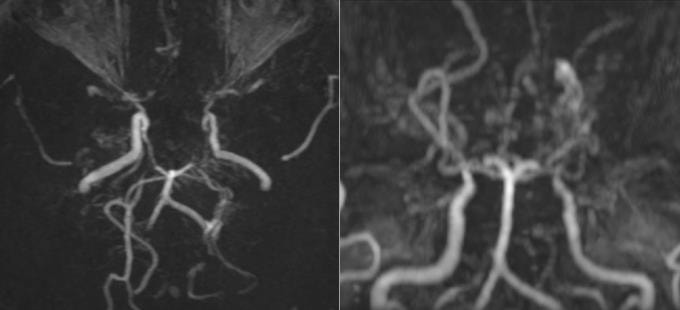

Kết quả khám lâm sàng nhận thấy người bệnh không có dấu hiệu thần kinh khu trú hay tăng áp lực nội sọ. Khi chụp cộng hưởng từ (MRI) sọ não, bác sĩ phát hiện hình ảnh tổn thương hẹp tắc động mạch cảnh trong hai bên và các nhánh, xung quanh có nhiều mạch máu nhỏ bất thường. Trên phim chụp mạch não, các mạch này tạo thành đám, tỏa mờ như "làn khói thuốc lá" - dấu hiệu đặc trưng của bệnh Moyamoya.

Bác sĩ Phạm Thị Yến, chuyên khoa Chẩn đoán hình ảnh, cho biết Moyamoya là một rối loạn mạch máu tiến triển, trong đó động mạch cảnh trong hộp sọ bị tắc nghẽn hoặc thu hẹp, làm giảm lưu lượng máu đến não. Điều này có thể dẫn đến hậu quả như vỡ động mạch và xuất huyết trong sọ. Các mạch máu nhỏ sau đó mở ra ở đáy não trong nỗ lực cung cấp máu cho não. Những cụm mạch máu nhỏ này không thể cung cấp máu và oxy cần thiết cho não, dẫn đến chấn thương não tạm thời hoặc vĩnh viễn.

Tên gọi của bệnh xuất phát từ ca bệnh lần đầu được phát hiện tại Nhật Bản. Moyamoya trong tiếng Nhật Bản là "làn khói thuốc lá", mô tả những mạch máu nhỏ bất thường, trông giống như làn khói thuốc.